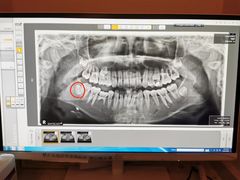

• 希望齿科(河西店)

• -希望齿科(河西店)

QI_648638458 | 20-12-05